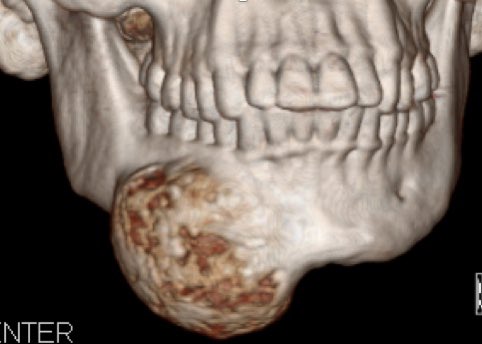

الغالبية من الحالات لا Ameloblastoma تظهر كتمدد في عظام الفك على هيئة مجموعة تكيسات متصلة وفي قليل من الحالات تظهر ككيس واحد متمدد داخل الفك والتشخيص يعتمد على نتيجة الخزعة (العينة)

١٧)

في حال كان الورم في الجزء الخلفي من الفك السفلي ومحيط بالعصب الفكي والذي يغذي الإحساس في الشفاة السفلى والذقن، يجب ابلاغ المريض بتأثر هذا العصب بعد الجراحة والذي سينتج عنه تنميل في المنطقة ويمكن علاجه بالرقعة العصبية لمحاولة اصلاح العصب وعودة جزء من الإحساس في المنطقة.